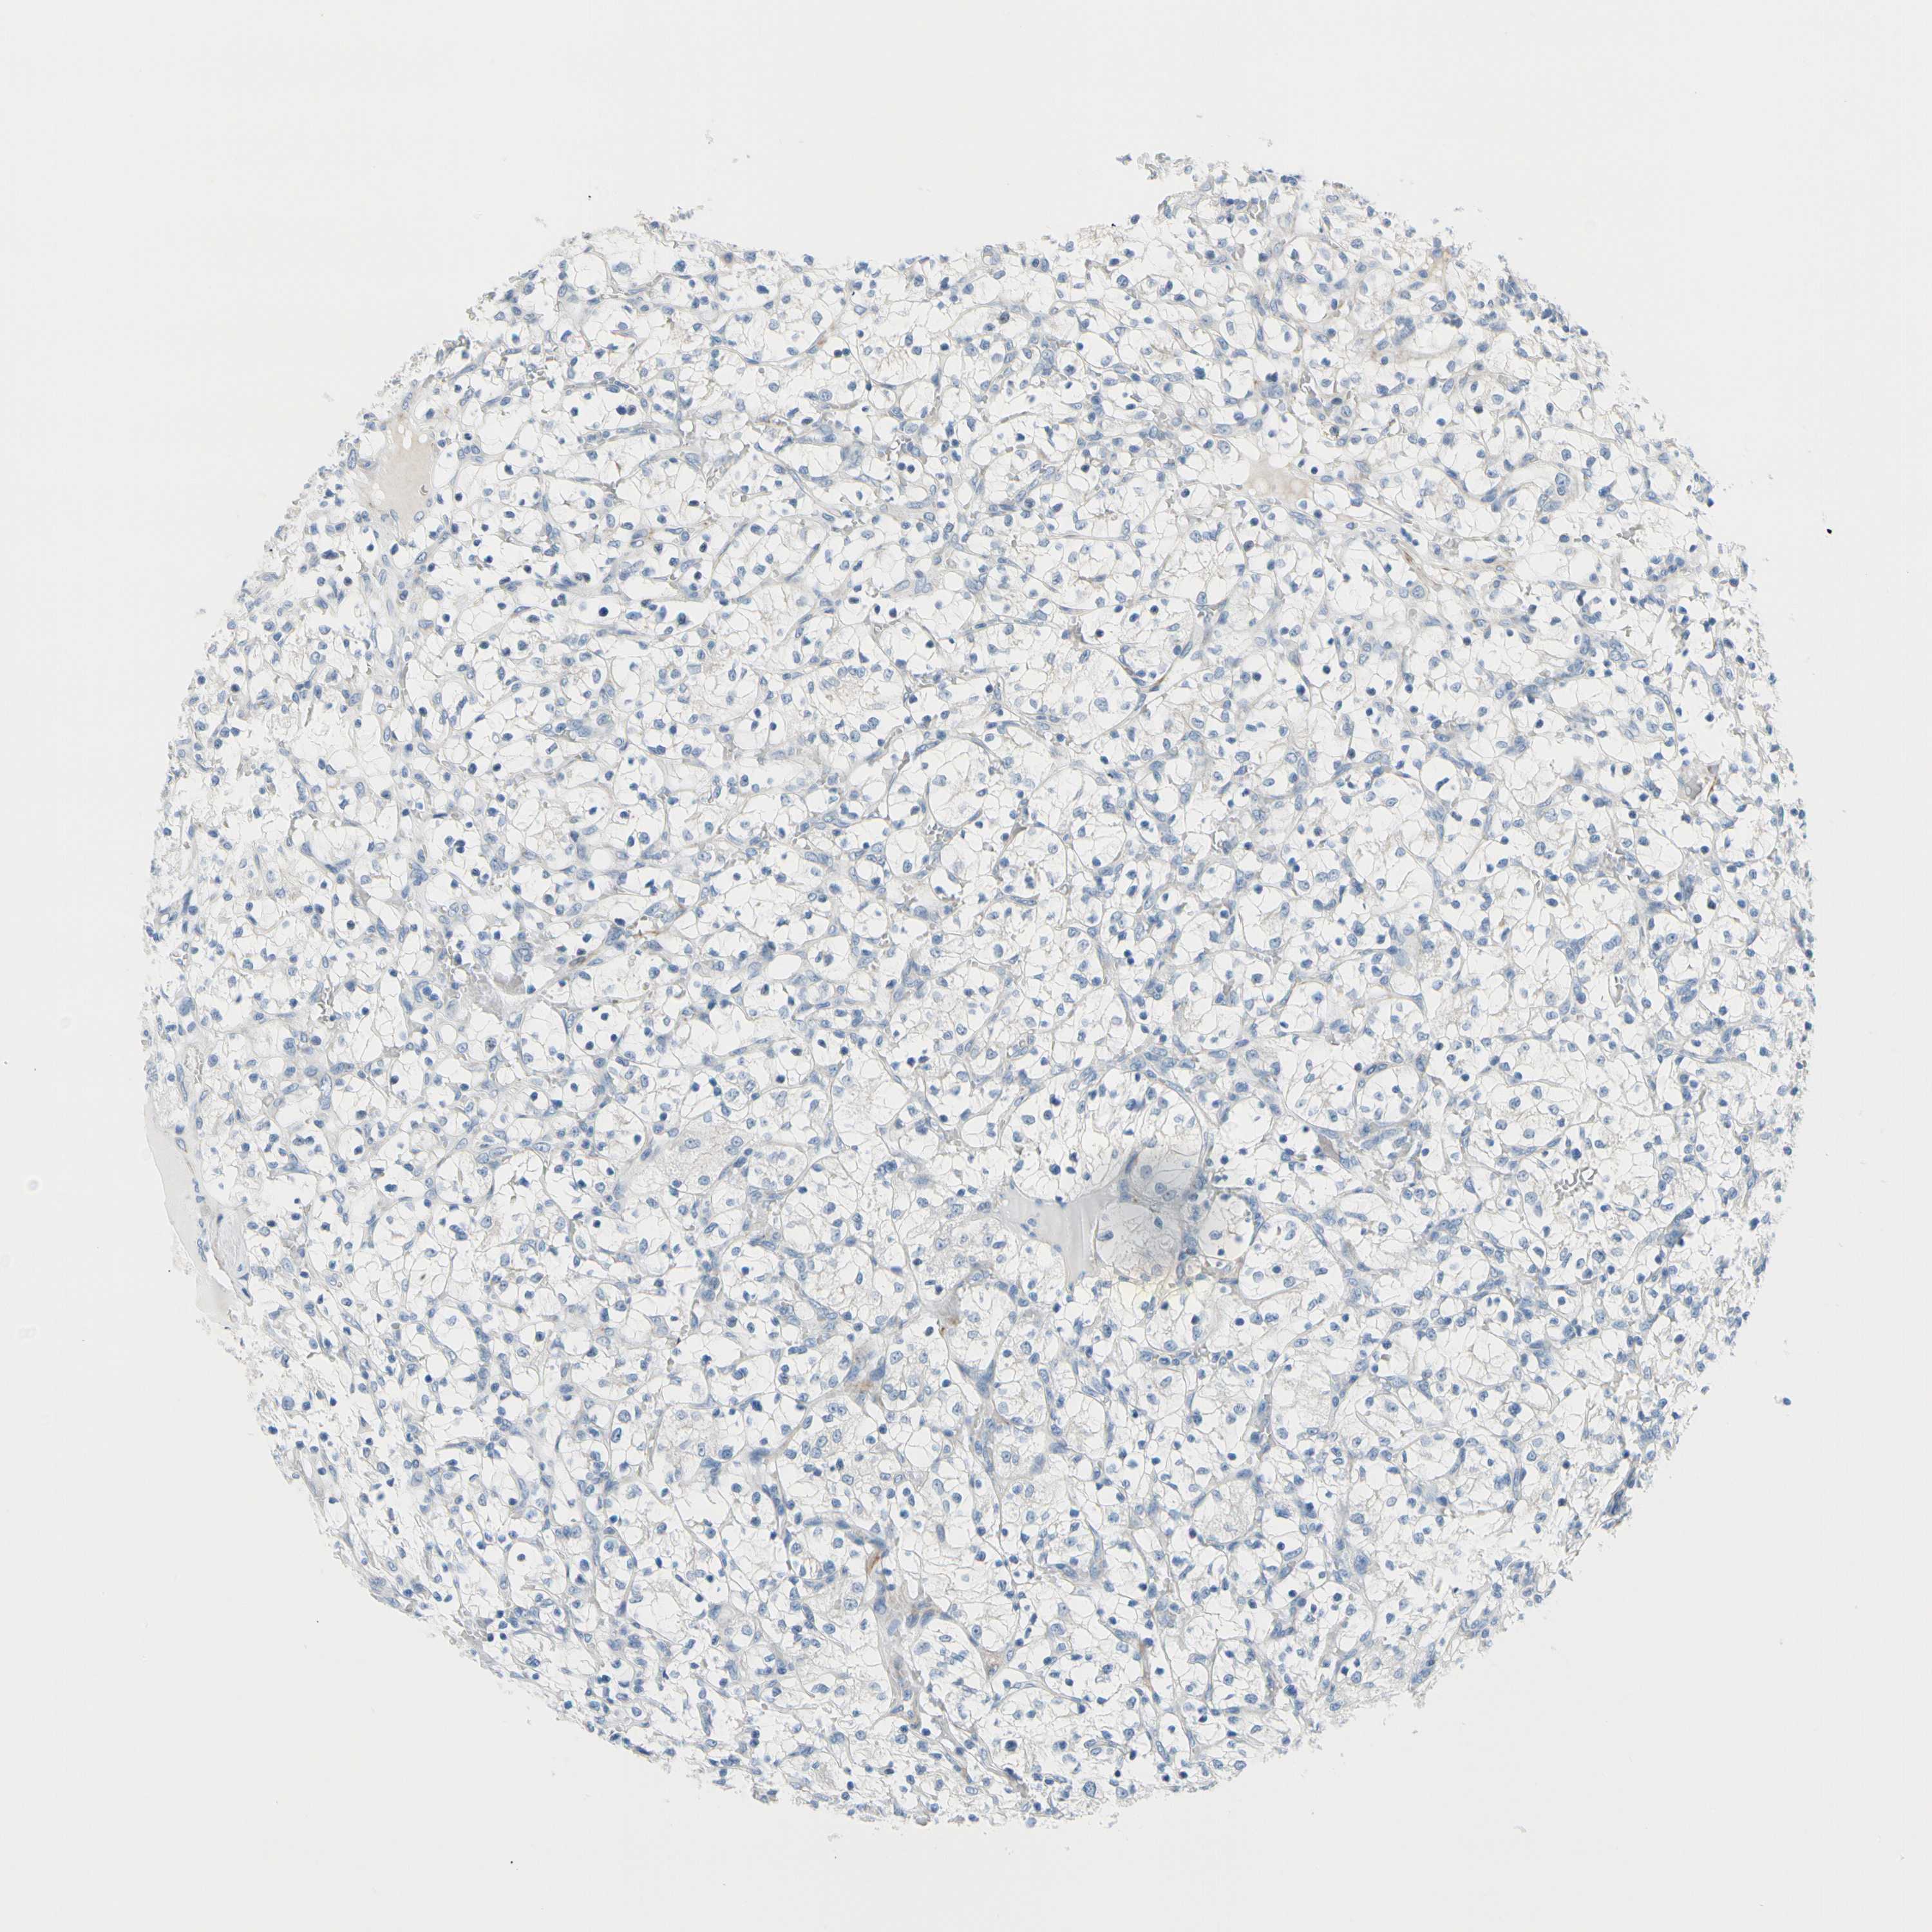

TCGA RNA samplesi

RNA-seq data is reported as average FPKM (number Fragments Per Kilobase of exon per Million reads), generated by the The Cancer Genome Atlas (TCGA) .

Normal distribution across the dataset is visualized with box plots, shown as median and 25th and 75th percentiles. Points are displayed as outliers if they are above or below 1.5 times the interquartile range. FPKM values of the individual samples are presented next to the box plot.

Average pTPM 0.2

Number of samples 100